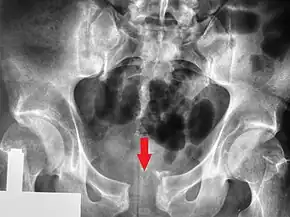

Radiologie standard

De nombreuses incidences radiologiques ont été évaluées par le passé. Une incidence de face du bassin est la première radiographie à réaliser dès l’admission d’un patient pour lequel on suspecte une lésion de l’anneau pelvien. Les radiographies standards révèlent 90 % des fractures du bassin[3].

Différentes incidences obliques sont indiquées en cas de suspicion de fracture du bassin non objectivable sur la radiographie de face. En en cas de suspicion de lésions particulières (fracture isolée du sacrum, fracture du cotyle…) des radiographies spécifiques peuvent être demandées.